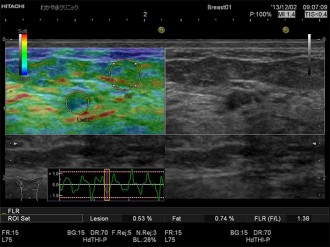

エラストグラフィとは、超音波検査でしこりの硬さを画像化する技術です。

その変形の程度を色で表したものがエラストグラフィで、周囲よりも硬い部分は青く表示されます。

がん組織は、周辺組織より硬い場合が多く、しこりの硬さを知ることは診断の一つの重要な情報となります。

乳がん検査の一つである超音波検査にエラストグラフィを組み合わせることで、硬さという診断に有用な情報を付加し、検査を受ける方にとっても負担の少ない優しい検査がおこなえます。